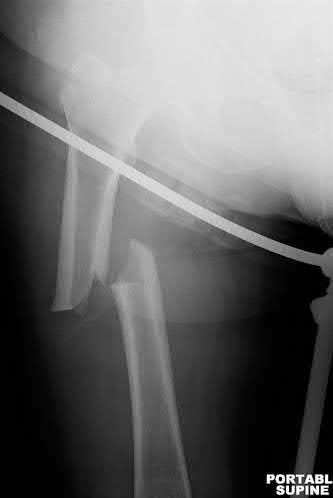

A 12-year-old obese boy presents with vague left thigh and knee pain. He is diagnosed with a Slipped Capital Femoral Epiphysis (SCFE) as seen in similar clinical scenarios. During percutaneous in-situ fixation, unrecognized penetration of the guide wire into the hip joint occurs. What is the most likely specific complication resulting from this technical error?

Chondrolysis is a severe complication of SCFE characterized by rapid destruction of the articular cartilage. While it can occur idiopathically, its most established iatrogenic cause is unrecognized intra-articular hardware penetration. The 'approach-withdraw' fluoroscopic technique is required during pinning to assure pins are entirely intraosseous. Avascular necrosis (AVN) is usually due to damage to the epiphyseal blood supply (retinacular vessels) secondary to the initial displacement, forceful closed reduction, or posterosuperior pin placement.